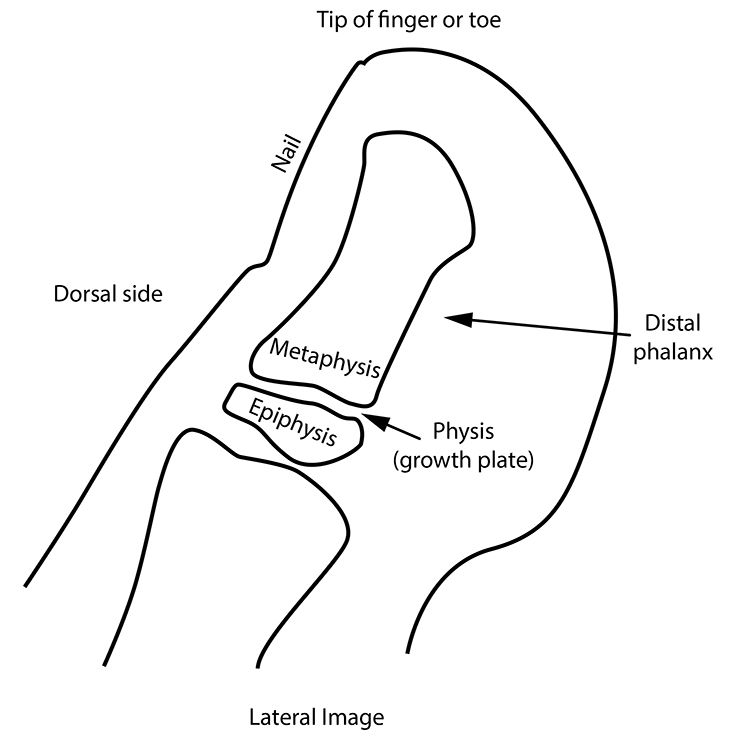

A Salter 2 fracture is a fracture that goes through the metaphysis and also the physis of a bone. The physis, or growth plate, is the cartilage allowing growth of the bone, which shows up on x-rays as a darker zone between the epiphysis at the end of the bone and the metaphysis, which is the shaft portion on the other side of the physis (see diagram 1).

A distal phalanx is the outmost bone of the bones in each finger or toe.